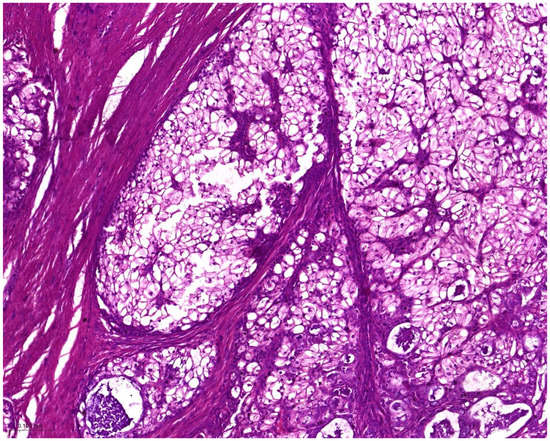

Hyalinizing clear cell carcinoma showed a nesting, cord-like, and trabecular arrangement. Ducts and small cysts could be observed. Squamous differentiation and mucocytes were commonly seen: sheets or nests of polygonal cells with clear cytoplasm and distinct cell borders. The cytoplasmic clearing was attributed to the presence of glycogen or other intracellular substances. The tumor cells exhibited nuclear atypia and a hyalinized stroma and fibrous septae separating the neoplastic fascicles. Although its name suggested the presence of clear cells, tumors consisting entirely of clear cells were rare, and some tumors lacked clear cells completely. Tongue HCCC displayed a pagetoid pattern of spread. The stroma varied from densely hyalinized, resembling a basement membrane to desmoplastic or fibrocellular. The juxtaposition of these two stroma types was largely characteristic of HCCC (Figure 2). Immunoreactivity of MEC and HCCC for ATF1 is shown in Figure 3.

Figure 2. Hyalinizing clear cell carcinoma. The clear cells display a translucent cytoplasm, giving them a clear appearance, which is distinct from other cell types that have noticeable granularity or eosinophilia. Additionally, the tumor stroma contains hyaline-like material (H and E, magnification 20×).